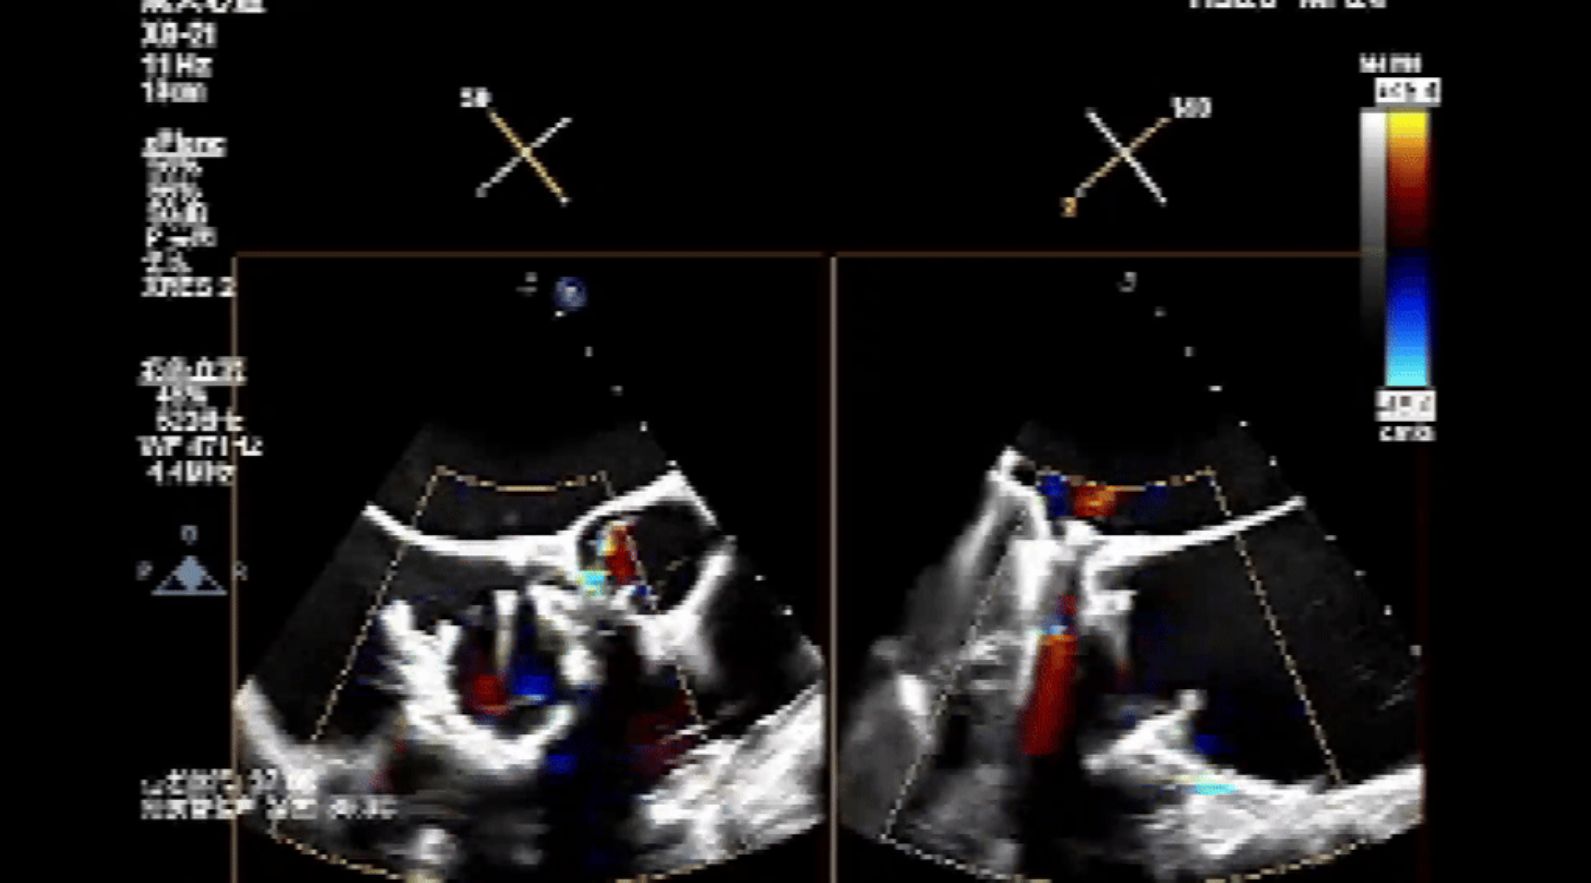

術前心臟超聲提示:三尖瓣大量返流,右心房容積明顯增大,三尖瓣瓣環顯著擴張。

術后心臟超聲提示:Lux-Valve Plus植入術后,三尖瓣瓣環處可見人工瓣膜回聲,未見返流,人工瓣膜穩定,瓣葉開閉良好,連續多普勒估測三尖瓣平均跨瓣壓差僅為1mmHg。